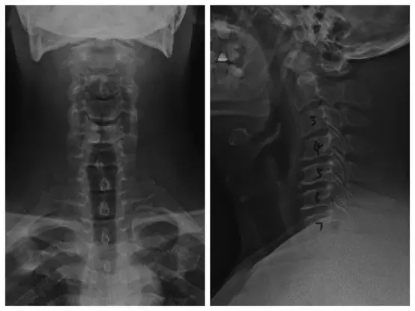

8月7日,我院为北京老知青颈椎病患者鲍师傅做了经后路颈椎椎板切开减压内固定手术,并将相关专题发在麦瑞骨科医院微信公众号上,反响热烈,热心粉丝们不断追问小麦:鲍师傅恢复怎么样了,手术预后如何啊……好吧,小麦就厚着脸皮去打扰鲍师傅一下下,鲍师傅恢复良好,手术效果明显,鲍师傅的家属说:“做完手术后明显跟术前不一样了,走路稳了,手脚麻木减轻,总想着出去多练练走路。”

朱副院长说,经后路颈椎椎板切开减压内固定术临床多应用单开门椎管扩大成形术,此法治疗多节段颈椎间盘突出、多节段后纵韧带骨化等脊髓型颈椎病收效甚好,既可以获得间接脊髓减压效果,同时也能保留更多颈椎活动功能。换句话说,就是用最小的代价,让患者受压脊髓不在被持续压迫以致变性,引发功能障碍,同时也最大限度地保留了颈椎的原始功能,让它继续为主人发挥功能,将功补过。

手术使用的钉板系统也有很多“科技内涵”。所用的钉板是微型钛板,利用钛合金良好的组织相容性,在手术开窗复位的时候用椎板和螺丝对椎骨进行固定,有利于螺钉—骨界面的长期稳定,实用性更强。这样,既对“门轴”侧起到牢固的稳定作用,也为“铰链”侧骨性愈合提供良好的环境;同时还会促进门轴侧顺利地达到骨性愈合,防止椎板原位还纳,在术后可提供即刻稳固、不变形的机械强度。

朱副院长说:“患者刚住院的时候,手脚无力而麻木感强烈,走路如同踩棉花般使不上劲,精神状态也不好。入院时大夫们判断为颈椎病,后来拍了片做了CT之后一核对,颈椎变形狭窄后韧带钙化,典型的脊髓型颈椎病。”脊髓型颈椎病为退变性颈椎病中最常见、最严重的类型之一,其致病病理是由于颈椎椎骨间连接结构退变,如椎间盘突出、椎体后缘骨刺、后纵韧带骨化等,导致脊髓受压或脊髓缺血,继而出现脊髓的功能障碍。在临床上多表现为手无力,麻木,写字拿筷子等都很困难,走路如踩棉花般,同时伴有肌萎缩、疼痛等症状。

而鲍师傅的颈椎就是颈椎管严重骨性狭窄,第3到第7椎间盘突出,合并钙化,颈5—7椎间隙水平前纵韧带增厚。变形椎骨和钙化韧带前后夹击,压迫脊髓,并且手术时发现其脊髓颜色也异于正常脊髓,幸好鲍师傅选对医院及时手术,要不然一旦脊髓受压变性严重,后果不堪设想。